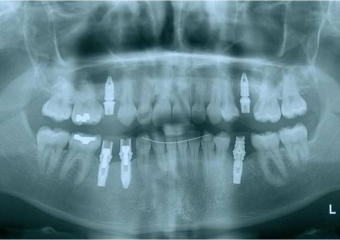

Raio x inicial, com agenesia de dentes permanentes

Raio após implantes instalados